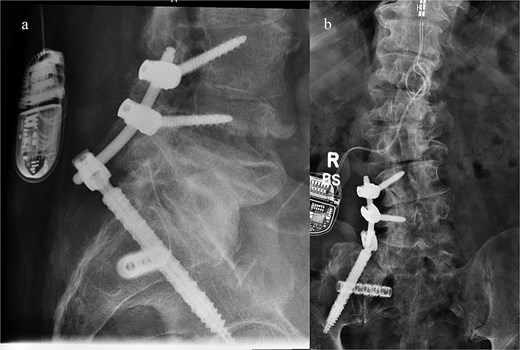

He was discharged home on postoperative day two, with instructions to remain toe-touch weight-bearing for three weeks. He was seen in the office two weeks after surgery. Lateral and antero-posterior pelvic radiographs showed good position of all hardware (Fig. 4). He reported mild incisional pain, but his preoperative pain had significantly improved. He was able to ambulate for the first time in years. Pain relief remains sustained three months after surgery.

Postoperative lateral (left) and AP (right) re-demonstrated good placement of the hardware.